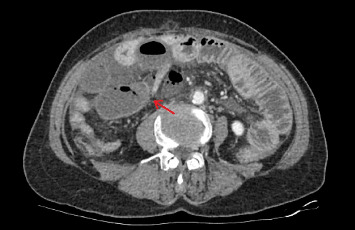

Background: Acquired ileal diverticulum is an extremely rare condition that occurs in the ileum and is caused by acquired factors. Strangulated intestinal obstruction, a life-threatening variant of bowel obstruction, is associated with exceedingly high mortality rates. Here, we present a case of acquired ileal diverticulum causing strangulated intestinal obstruction, which was treated at our hospital. Case Report: A 65-year-old female with no previous history of intestinal obstruction presented with acute abdominal pain. An exploratory laparotomy revealed an acquired ileal diverticulum and an internal hernia. Conclusion: Acquired ileal diverticulum leading to strangulated intestinal obstruction is rare. Clinicians should consider the possibility of this disease when encountering intestinal obstruction patients with no history of abdominal surgery.